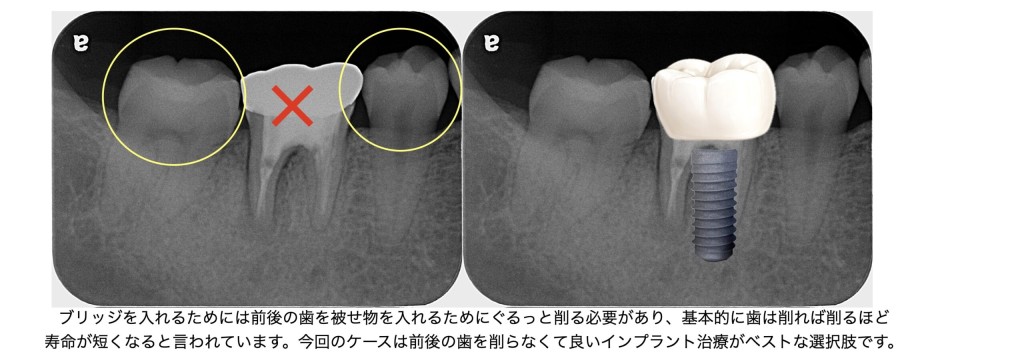

右下6番の前後の歯(5番・7番)はどちらも健康で、神経も生きている天然歯でした。

ブリッジ治療では、これらのきれいな歯を大きく削らなければならず、さらに土台として長期間強い負担がかかります。

歯を長く残すという観点から、天然歯を削らないインプラントは理にかなった選択肢です。